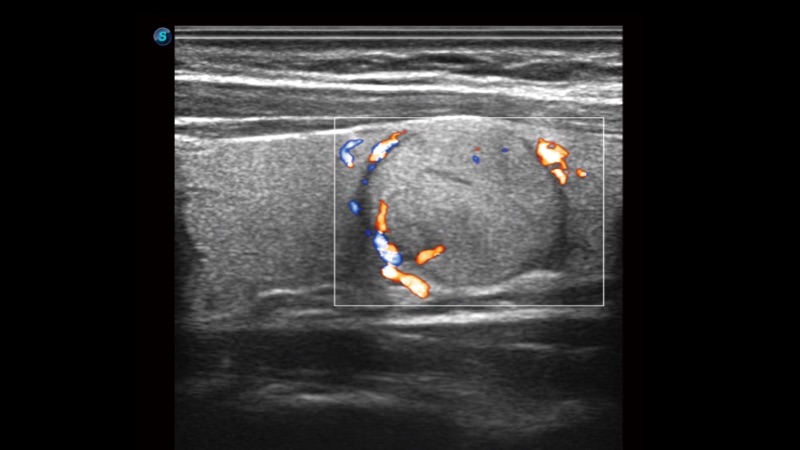

μ-Scan+新一代微米成像技术

新一代微米成像技术大大提高了器官和病变的可见性。高清对比度分辨率将抑制斑点噪声,同时保持真实的组织结构。

弹性成像

弹性成像无需高频度外力作用可真实反映组织的形变,具有良好的重复性,更早地洞察潜在的病理学特征。